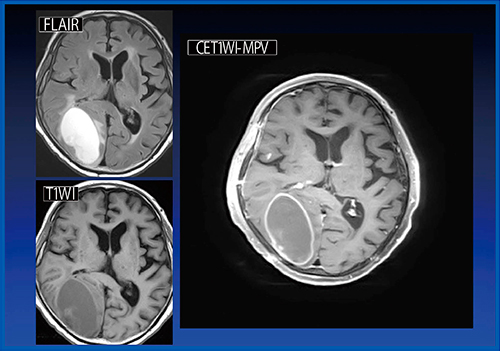

症例2(図2)は,多発脳転移症例である。造影T1WI-MPVは,腫瘍と脳実質のコントラストが高く,血管の信号が抑制されるため,基底核や前頭弁蓋部などの微小な増強効果も容易に検出できる。多発性病変では新規病変の検出や過去画像との比較が容易となり,臨床的有用性がきわめて高い。また,グラディエントエコー法との比較では,上記の利点に加え,磁化率効果に伴う画像の歪みや血管拍動によるアーチファクトが抑制されることがメリットとして挙げられる。ただし,転移と偽病変(残った血管の信号)との鑑別には注意が必要である。

図2 症例2:多発脳転移症例(70歳代,男性)